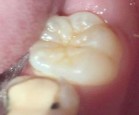

Bệnh nhân: Ng. Bá Tuấn Đ. 6 tuổi, răng 36, mã BA 6320/17

Sau sáu tháng. ICDAS: 2; Di: 21 | Sau chín tháng. ICDAS:1; Di: 19 | Sau 12 tháng. ICDAS: 1; Di: 14 |